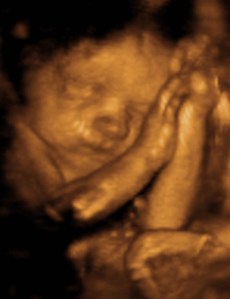

NOSE! Just look at that little pinchable nose! Here we are, at 29 weeks, and believe it or not, there appears to be a REAL baby in my belly! WHOA! talk about sci-fi crazy talk! She’s got a full head of hair, no you can’t see it….that black stuff that might look like hair, is actually her favorite pillow…my bladder. But she has, little hands and feet, pouty lips and appears to be a super cuddler! YAY!